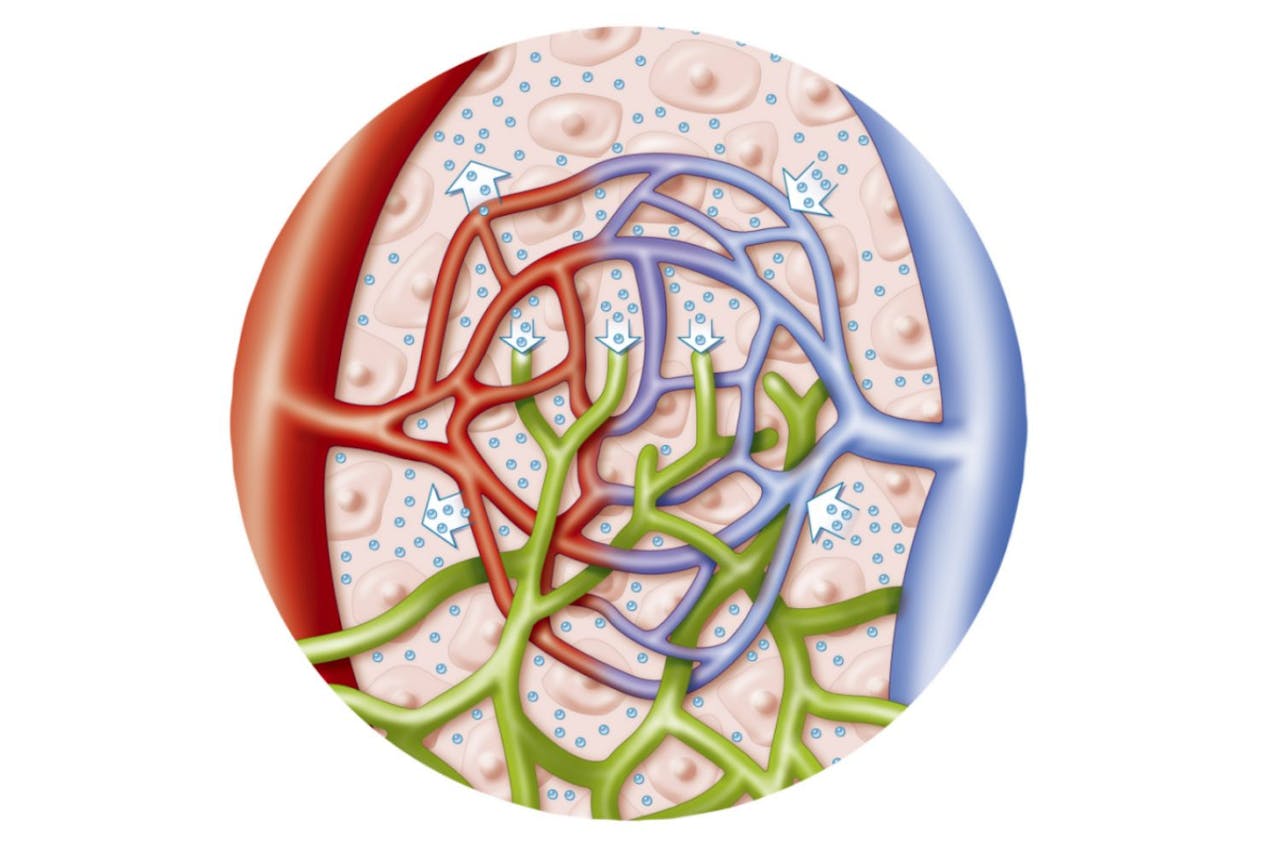

Изображения и схемы: как выглядит лимфа